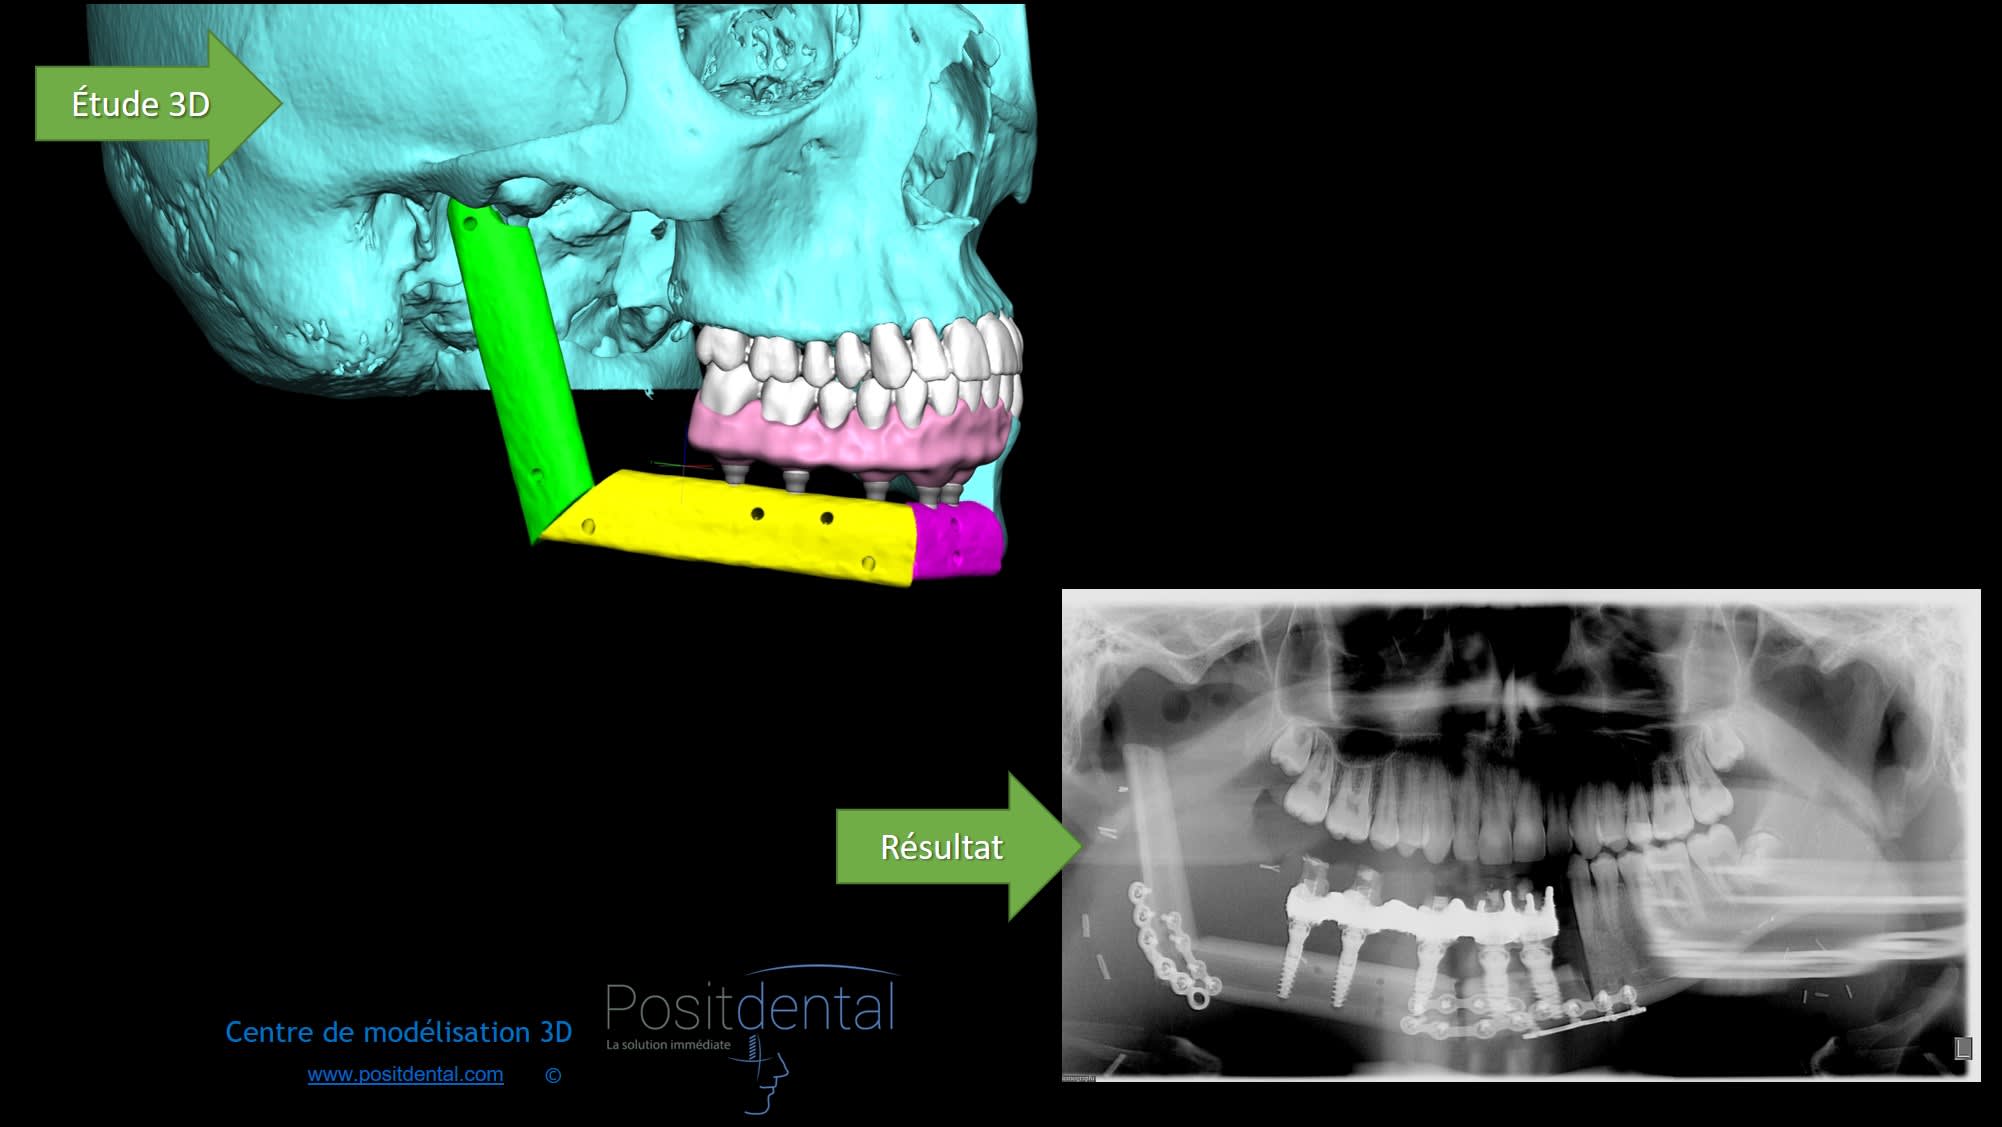

Les indications clinique ce n'est pas moi qui les poses par contre la simulation implantaire et les DMSM avec toute les justificatifs et données technique pour qu'une fois validées le praticien puisse réalisé ça oui

Modélisation 3d et résultat clinique hdgupg - Eugenol

Mais pourquoi avoir gardé cette pauvre molaire mandibulaire ???... C était pour être sûr d avoir assez de biofilm pour contaminer les sites ??

T as la pano du patient avant son edentation ?

Tu as du lire dans des études scientifique que même des années post extraction chez l'édenté total les bactéries responsables des parodonties sont présentes.

Merci de tes conseils et pour ce cas tu as un avis ?

Modélisation 3d et résultat clinique ygsom6 - Eugenol

Oui et c'est pour cela que je te parle bien de biofilm... les mots on un sens.

tres honnêtement, la conservation de cette molaire questionne... pourquoi l'avoir gardée ? quelle est son rôle ?